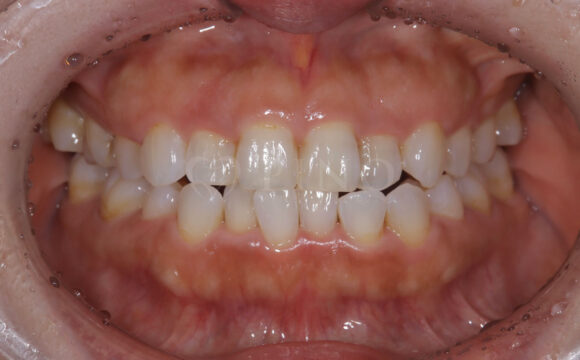

症例4:噛み合わせが深く、下の歯が見えないのが気になる(10代女性)

主訴 噛み合わせが深い、下の歯が見えない 診断名 過蓋咬合(かがいこうごう) 治療方法 マウスピース全顎矯正 抜歯 なし オルソパルス なし 治療期間 1年1ヶ月 費用 746,000円 副作用・注意点 矯正後の後戻りを防ぐためリテーナーの使用が必要となる -